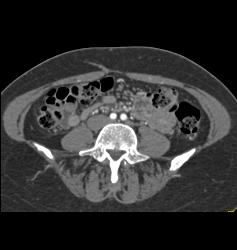

DIEP Flap Planning in 3D